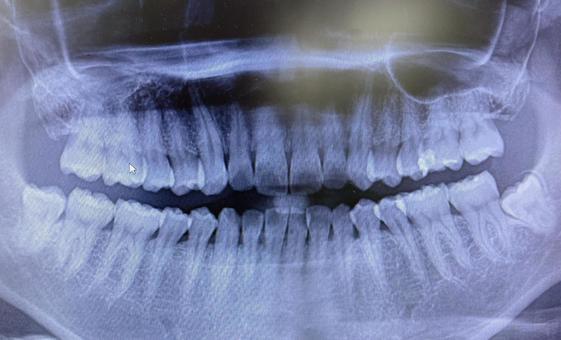

「叢生」は、一般的に「乱ぐい歯(らんぐいば)」「八重歯(やえば)」「ガタガタの歯並び」などと呼ばれる状態で、日本人に非常によく見られる不正咬合(ふせいこうごう:良くない噛み合わせ)です。

<叢生の状態>

顎(あご)の骨の大きさに対して、歯のサイズが大きすぎたり、歯が並ぶスペースが不足していたりするために、歯がデコボコに重なり合って生えている状態を指します。